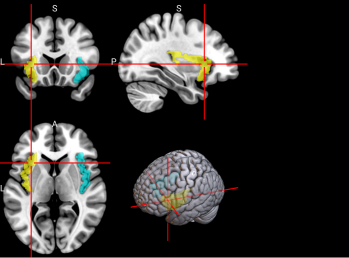

65,

66

L & R Inferior parietal gyrus, excluding supramarginal and angular gyri (IPG)

The inferior parietal gyrus is involved in attentional, semantic, and social cognitive functioning [65].

/word/media/image14.png/word/media/image14.png